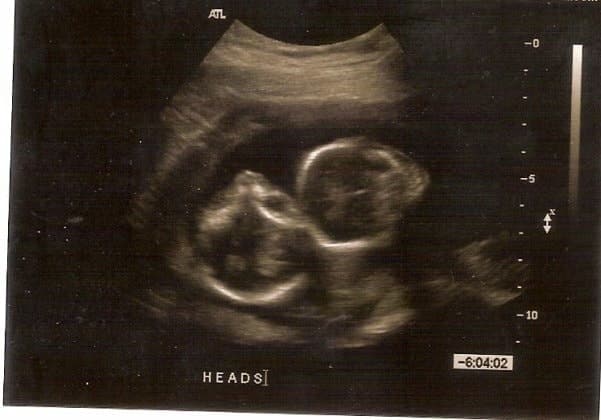

- Ultrasound Photos at 17 Weeks Pregnant With Twins

Ultrasound Photos at 17 Weeks Pregnant With Twins